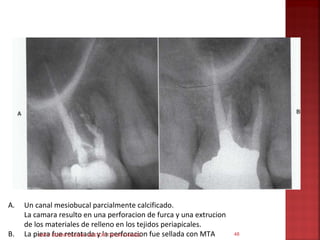

A.   Un canal mesiobucal parcialmente calcificado.

La camara resulto en una perforacion de furca y una extrucion

de los materiales de relleno en los tejidos periapicales.

B.   La pieza ODONTOLOGIA- NESTOR TAFUR CHAVEZ fue sellada con MTA

C. En la radiografia tomada a los 3 años

no se evidencia signos patologicos en el

area reparada.